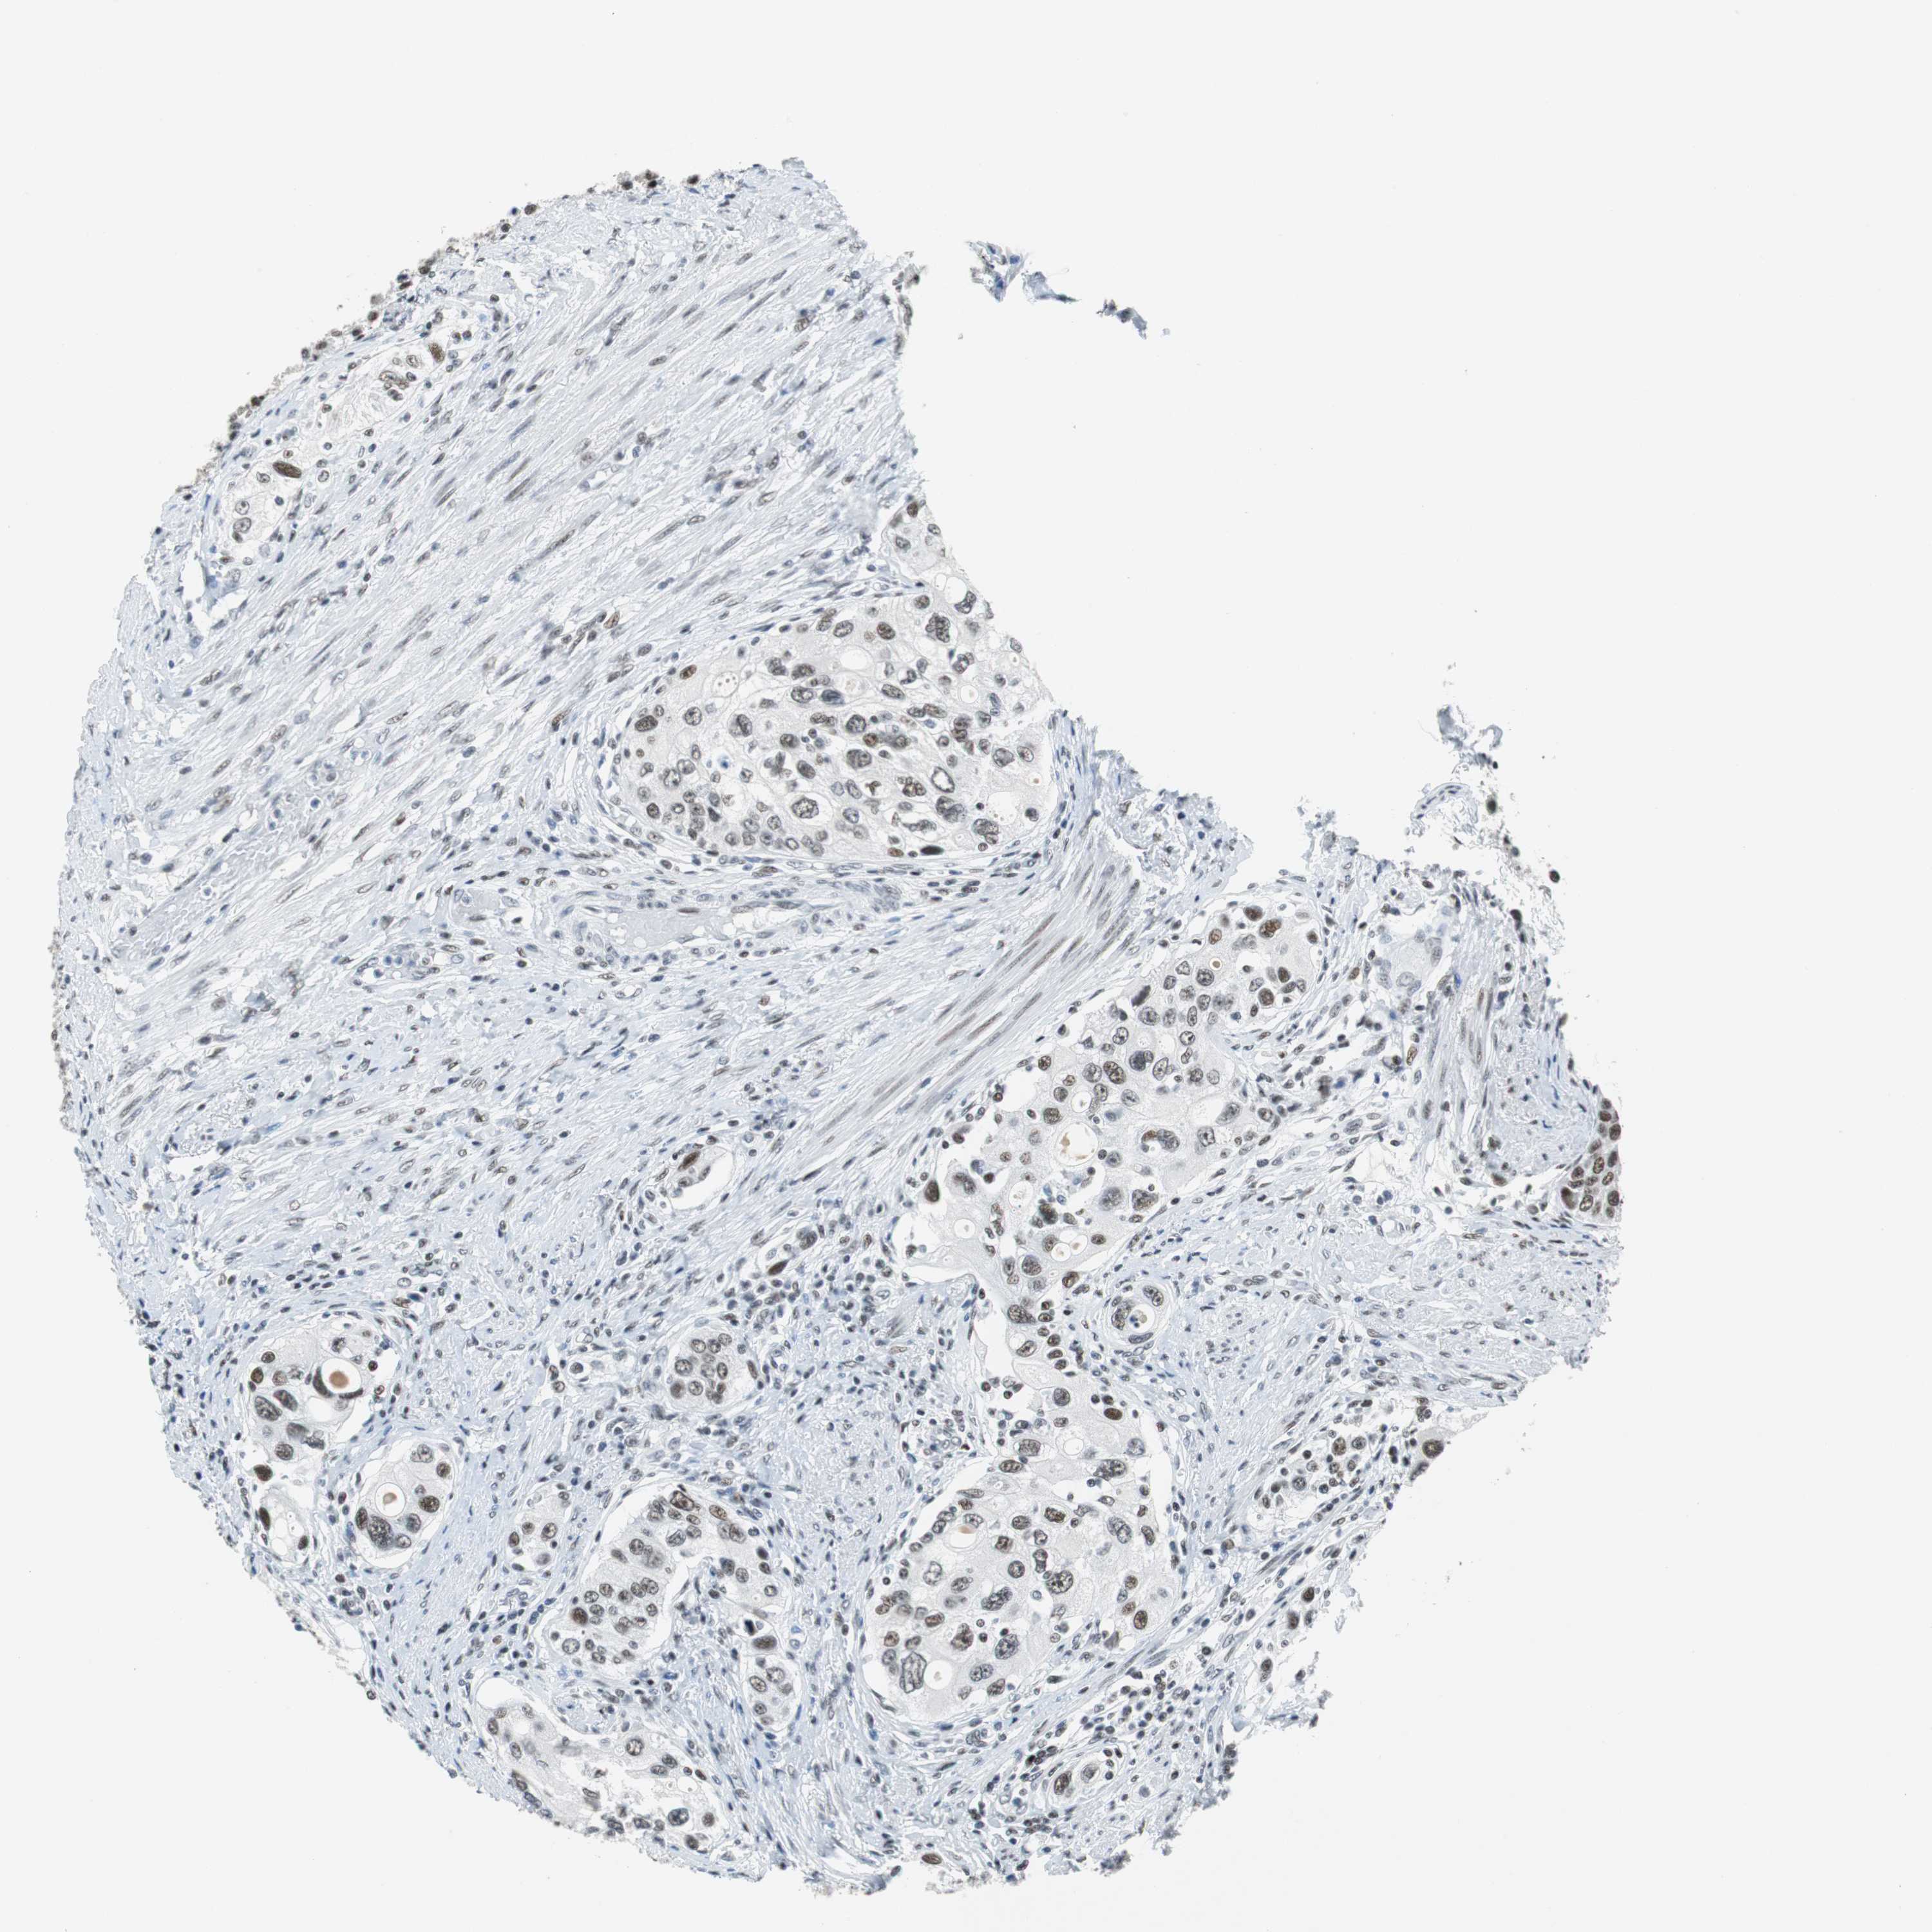

UROTHELIAL CANCER - Protein expressioni

A mouse-over function shows sample information and annotation data. Click on an image to view it in a full screen mode. Samples can be filtered based on level of antibody staining by selecting one or several of the following categories: high, medium, low and not detected. The assay and annotation is described here.

Note that samples used for immunohistochemistry by the Human Protein Atlas do not correspond to samples in the TCGA dataset.

Antibody stainingi

Antibody staining in the annotated cell types in the current human tissue is reported as not detected, low, medium, or high, based on conventional immunohistochemistry profiling in selected tissues. This score is based on the combination of the staining intensity and fraction of stained cells.

Each image is clickable and will lead to virtual microscopy that enables deeper exploration of all samples and also displays staining intensity scores, fraction scores and subcellular localization as well as patient and tissue information for each sample.

Antibody HPA052052

Antibody CAB005583

Antibody CAB072336

Urothelial carcinoma, High grade

Urothelial carcinoma, Low grade

Urothelial carcinoma, NOS